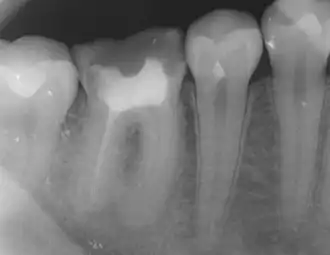

The body's response to microbial invasion